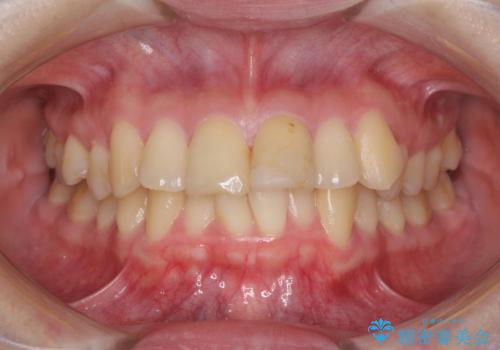

上下前歯のデコボコをきれいに インビザラインによる矯正治療

- 前歯の著しい叢生と前突感を気にして来院された患者様です。

叢生が強いため、事前に前歯をワイヤー矯正で速やかに叢生を解消し、その後はインビザラインにて矯正治療を行うこととしました。

ワイヤー矯正を併用したことで前歯の叢生を速やかに解消することができました。

一方口元の突出感を改善するために時間がかかり、2年超を要しましたが、満足のいく仕上がりとなりました。